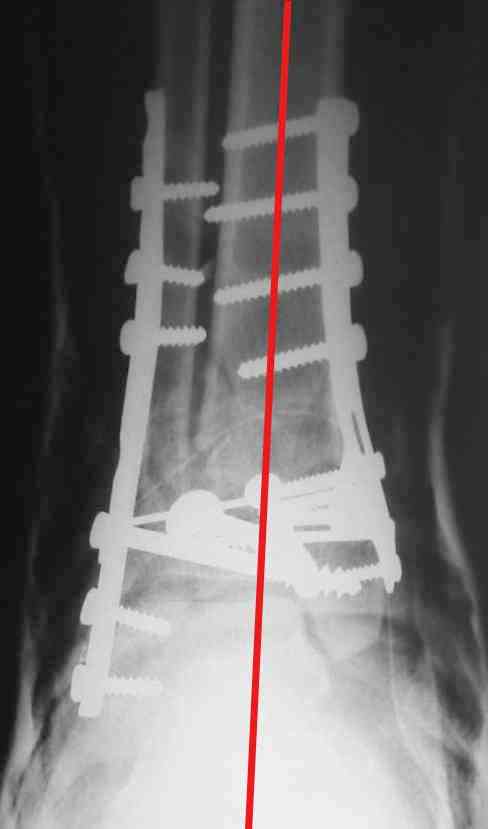

На представленном снимке видно, что эпифиз смещен латерально.

Сейчас с этим ничего не сделать, похоже.

Однозначно сказать сложно.Расстояние между тараном и медиальной лодыжкой меньше чем между тараном и крышей большеберцовой кости.Это может быть за счёт не правильной укладки.Пока не отчаиваетесь.Главное вы поняли принцип.Сделайте несколько проекций прямых и посмотрим.Для всех интересно.С уважением

Пластина лист клевера есть в варианте DCP -динамическая компрессирующая пластина.В ней все отверстия круглые,развальцованные отверстия под винт 3,5, чтобы шляпка винта не торчала.Винты 4,5 тоже проходят в эти отверстия, но шляпка не погружается.Могут быть проблемы с мягкими тканями.Пластина LCP -пластина с блокированием.В каждом отверстие пластины нарезана резьба и на шляпке винта такая же.Получается блок винт-пластина-кость.Очень крепко.Первоначально она готовилась для остеопороза, много лет в Давосе её разрабатывали.Я видел там первые образцы ещё в 1995 году, а начали они в 80-годах.Насчёт оси по рентгенограмме пока не согласен пусть сделают хорошую, правильную прямую проекцию.С уважением Дрягин